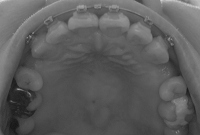

上から。変化なし。

2007/06/11撮影

2007/07/30撮影